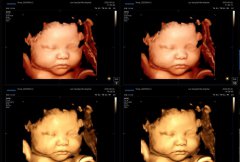

亲爱的准爸爸妈妈们: 7月28日,国家重磅推出《育儿补贴制度实施方案》,2025年起每孩每年可领3600元补贴,直至3周岁!连2025年1月1日前出生还没满3岁的娃,也能按月折算拿到补贴!这可是新中国成立以来,头一回这么大范围、...